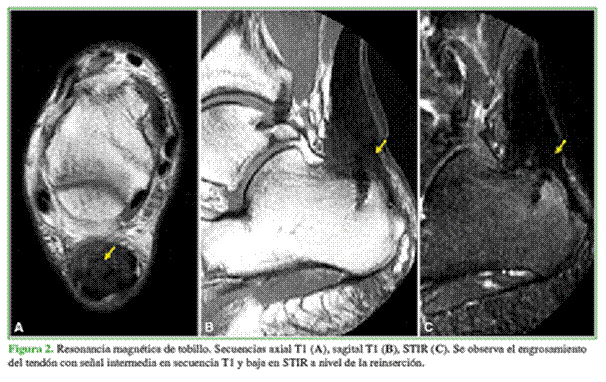

En la radiografía, se observa un tendón de Aquiles engrosado con elementos de inserción a nivel del calcáneo (Figura 1).

La RM confirma los hallazgos de tendinopatía crónica sin cambios de señal significativos en la inserción distal (Figuras 2 y 3).